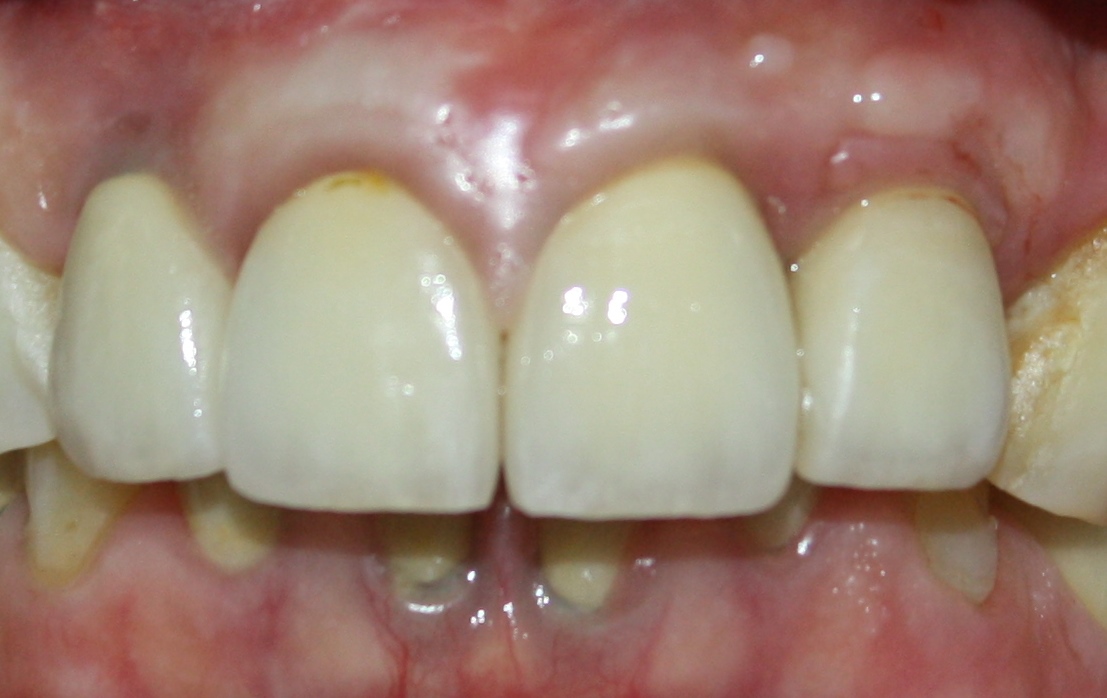

Вместе с ним мы сделали из этого:

вот это:

В итоге, на этапе временного протезирования у нас получилось вот это:

он меняет временные коронки на более естественные. С этого момента мы уже можем оценить первые результаты нашей работы:

и фиксируют их на зубах и имплантах. Это фотография сразу после фиксации:

вот так это выглядит со стороны. Учтите, что это — простая металлокерамика на простых абатментах. Никаких сверхнаворотов или сложно-выдуманных решений:

Вот фотография, сделанная на одном из профилактических осмотров, примерно через полгода после завершения протезирования:

Прошло еще полгода:

Давайте еще раз вернемся к началу:

И посмотрим, что получилось в конце:

или: